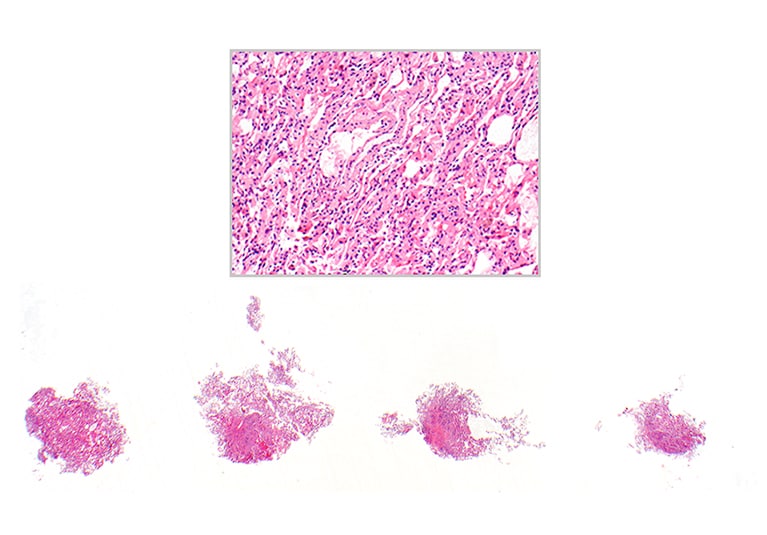

Lung allograft with focally collapsed and crushed alveoli

A conventional transbronchial biopsy of a lung allograft with focally collapsed and crushed alveoli. Hematoxylin-eosin stain, 12.5 times magnification; insert 200 times magnification.